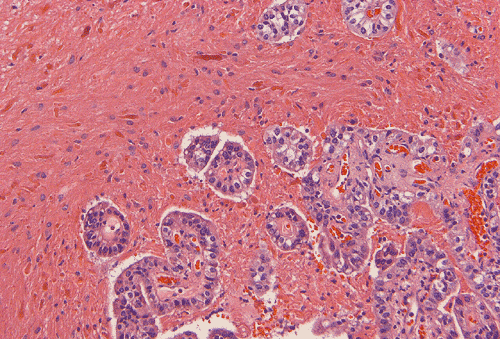

Permanent sections show a papillary epithelial neoplasm with invasion into the brain parenchyma (Panel G, H, and I ). In all areas the tumor cells maintained a single layered architecture. While a papillary structure is present in some area, the tumor cells arrange in a back-to-back cystic architecture intervened by a thin layer of fibrovascular stroma (Panel J). The nuclei are rather bland and monotonous. Mitotic figures are not readily seen  (Panel K). On immunohistochemistry, practically all tumor cells strongly express S100 protein (Panel L) and vimentin (Panel M). Most tumor cells are positive for cytokeratin (AE1/AE3) (Panel N). GFAP is expressed by some tumor cells (Panel O). The Ki-67 labeling index is about 1-2% (Panel P).